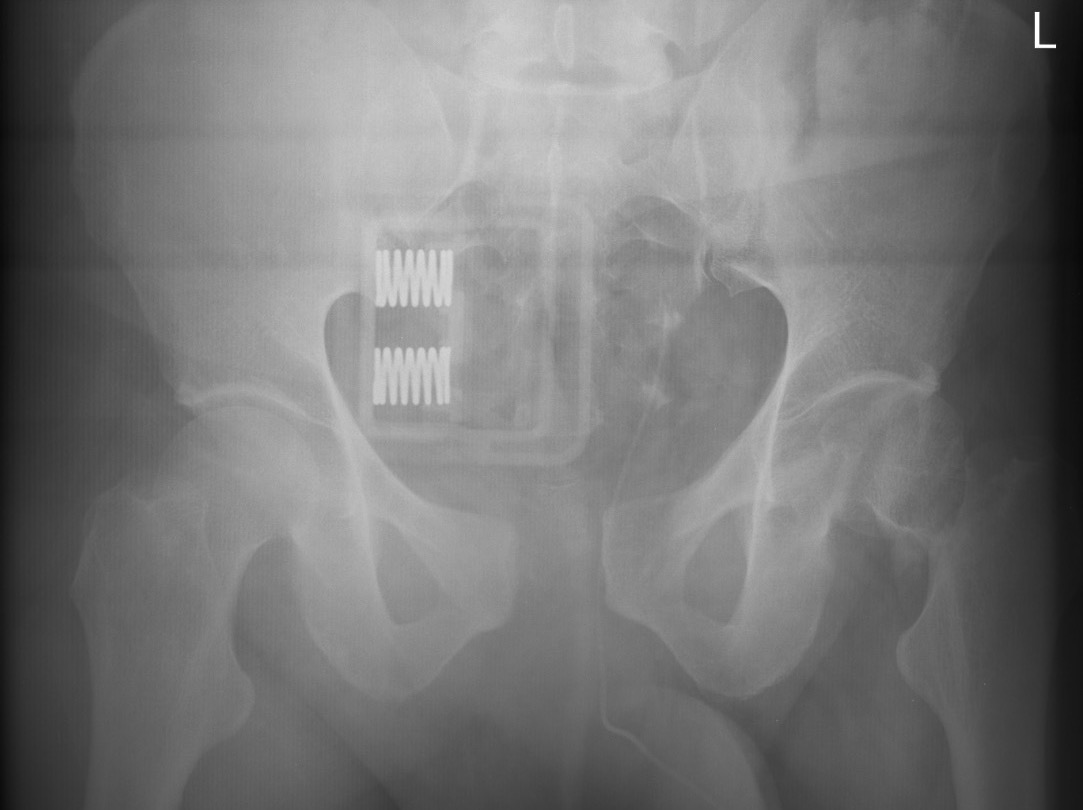

APC pre binderAPC post binder

APC fracture pre- and post binder (note improper position cranial to trochanters)